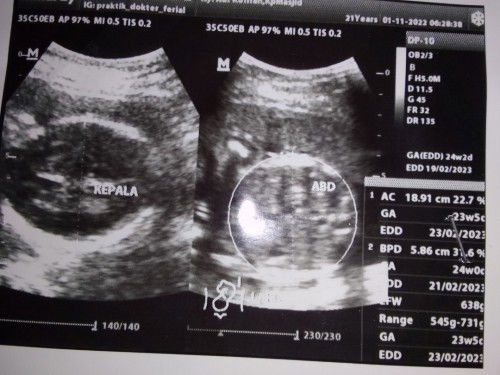

Barangkali disini ada yang sama ky aku bun. Usia kandungan aku 32minggu hpl insyaallah tanggal 19feb

Barangkali disini ada yang sama ky aku bun. Usia kandungan aku 32minggu hpl insyaallah tanggal 19februari. Tapi aku lagi khawatir Bun,takut asi ku gak keluar karena payudara aku kecil banget 😭 kira2 ada yang sama gak ky aku payudaranya kecil. Mau minum pelancar ASI kira2 yang bagus apa ya Bun?😓🙏#seriusnanya #bantusharing